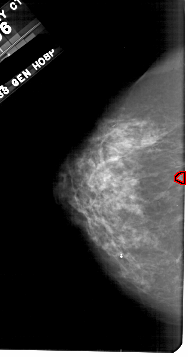

A_1709_1.RIGHT_MLO

RIGHT_MLO LINES 5491 PIXELS_PER_LINE 2611 BITS_PER_PIXEL 12 RESOLUTION 43.5 NON_OVERLAY